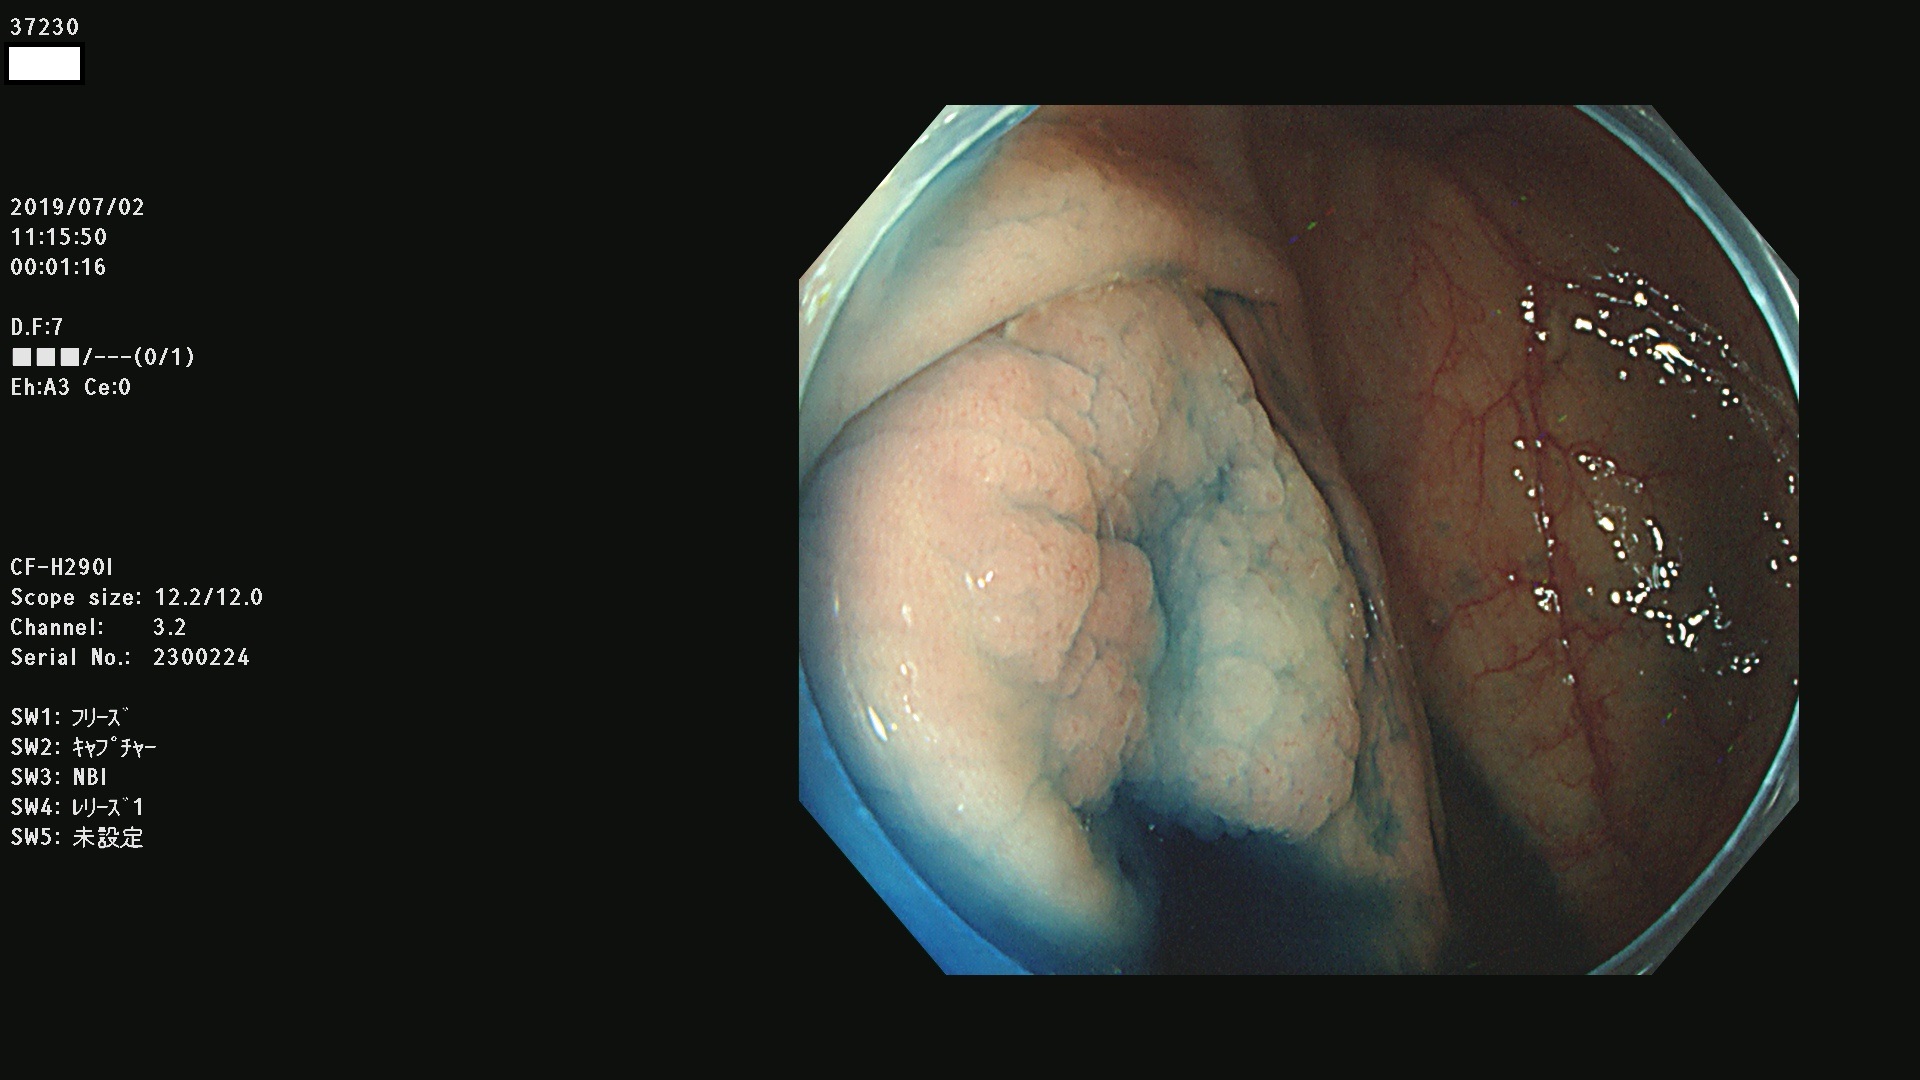

37200 37203 37204 37207 37208 37209 37210 37211 37212 37213 37214 37215 37216 37217 37220 37221 37222 37224 37225 37228 37229 37230 37232 37233 37234 37235 37236 37238 37241 37242 37243 37244 37245(SSAPのみ) 37247 37249 37250 37251 37252(SSAPのみ) 37254 37256 37257 37258 37259 37260(SSAPのみ) 37261(SSAPのみ) 37262 37263 37264 37265 37266 37267 37268(SSAPのみ) 37269 37271 37273 37274 37276 37277 37278 37279 37280 37281 37282 37284(SSAPのみ) 37285 37286 37288 37289 37290 37292 37293 37295 37296 37297(SSAPのみ)

発見困難で危険性の高い平坦型病変(上記100名より抽出)